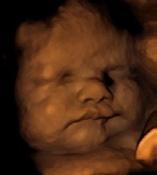

3D/4D ultrasound

Peek at Me 4D